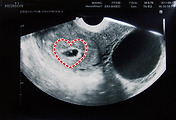

지난번 병원에 갔을 때 첫 기영아 검사를 했었는데 이상 없다내요. 우리 아기 잘 클 거란 믿음 있었지만, 그 믿음을 다시 한번 확인시켜 주니 기쁘네요. 아래는 초음파 사진으로 10주차와 12주차입니다. 2주의 기간동안 2배정도 자랐었는데 이번엔 더욱 많은 성장을 했어요.

세상에서 가장 사랑하는 사람의 배 속에서 내 아이가 커가는 모습이란... 아직은 아이의 성장하는 모습을 초음파 사진의 실루엣과 성장의 크기를 나타내는 cm(센티미터)로 밖에 볼수 없지만 잘 자라고 있다니 그 걸로도 충분합니다.